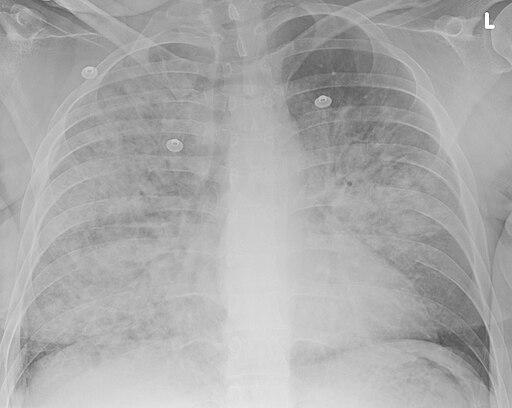

Neumonía por aspiración

Doc James, CC BY-SA 4.0, via Wikimedia Commons

Una radiografía de tórax.